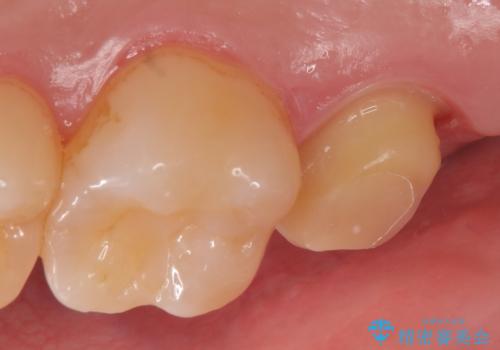

その後オールセラミッククラウンによる補綴を行いました。

今回用いたオールセラミッククラウンはジルコニアフレームという白い素材の上にセラミックを盛っているため、審美性が非常に高いのが特徴です。

また、ジルコニアは人工ダイヤモンドの材料にも使われているほど高い強度を持っており、そのためオールセラミッククラウンは審美性だけでなく、奥歯やブリッジの補綴も可能とするクラウンです。